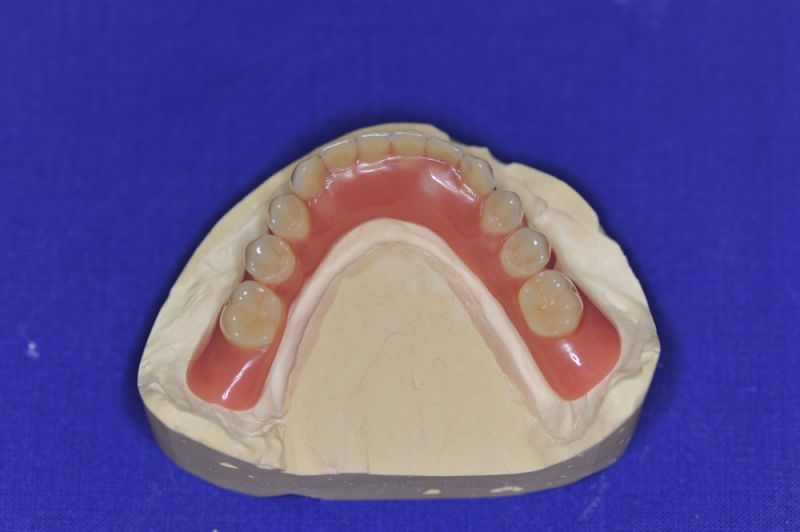

Der Patient erhält heute eine neue implantatgetragene Prothesenrekonstruktion im Ober- und Unterkiefer.